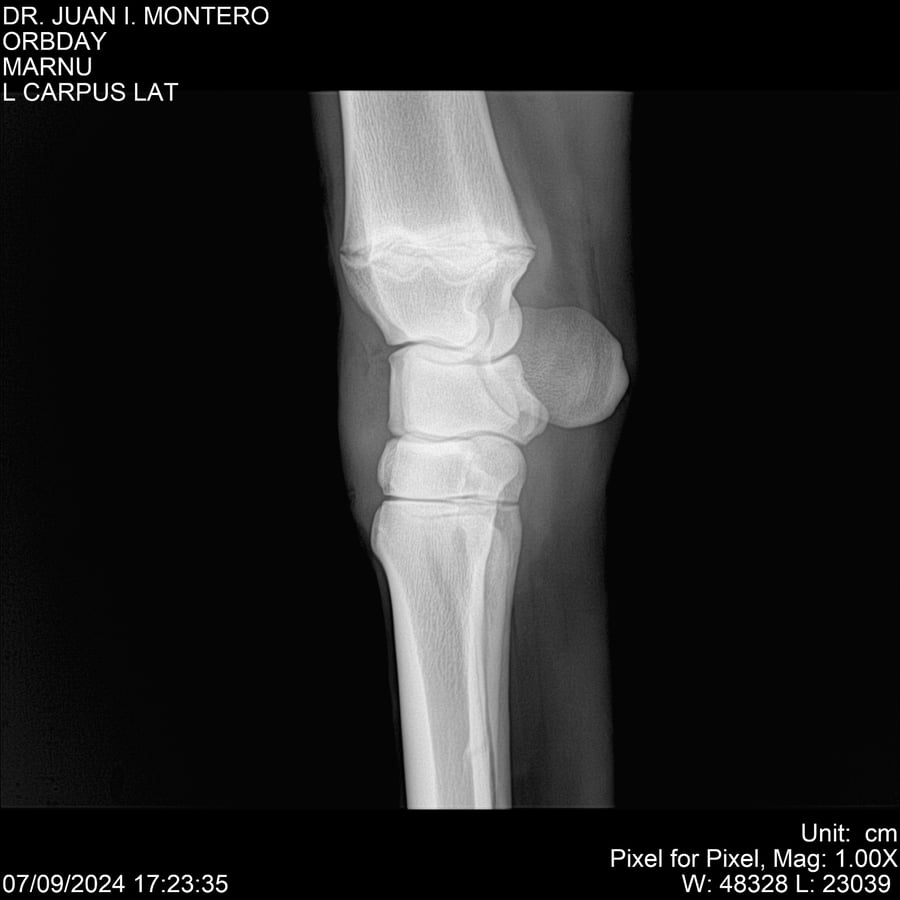

• Empresa: Abelenda N. R., Walter Hugo